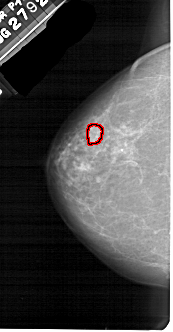

A_1536_1.RIGHT_MLO

RIGHT_MLO LINES 5401 PIXELS_PER_LINE 2821 BITS_PER_PIXEL 12 RESOLUTION 43.5 NON_OVERLAY

FILE: A_1536_1.LEFT_MLO.OVERLAY

TOTAL_ABNORMALITIES 1

ABNORMALITY 1

LESION_TYPE MASS SHAPE OVAL MARGINS ILL_DEFINED

ASSESSMENT 4

SUBTLETY 3

PATHOLOGY MALIGNANT

TOTAL_OUTLINES 1

BOUNDARY